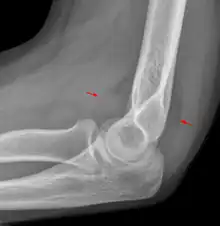

Fat pad sign

The fat pad sign, also known as the sail sign, is a potential finding on elbow radiography which suggests a fracture of one or more bones at the elbow. It may indicate an occult fracture that is not directly visible. Its name derives from the fact that it has the shape of a spinnaker (sail).[1] It is caused by displacement of the fat pad around the elbow joint. Both anterior and posterior fat pad signs exist, and both can be found on the same X-ray.

In children, a posterior fat pad sign suggests a condylar fracture of the humerus. In adults it suggests a radial head fracture.

The fat pad sign is invaluable in assessing for the presence of an intra-articular fracture of the elbow. An anterior fat pad is often normal. However a posterior fat pad seen on a lateral x-ray of the elbow is always abnormal. The patient will be unable to flex their elbow and requires orthopaedic input.[2]